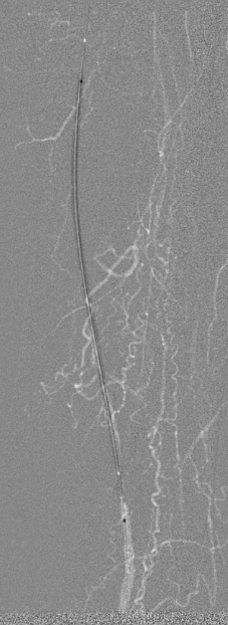

图为:导丝通过病变 置入保护伞 使用Turbohawk定向旋切

图为:股总动脉珊瑚礁病变定向旋切结果股浅动脉段尚未完成定向旋切

图为:血管准备:股浅旋切后球囊全程节段逐级式扩张